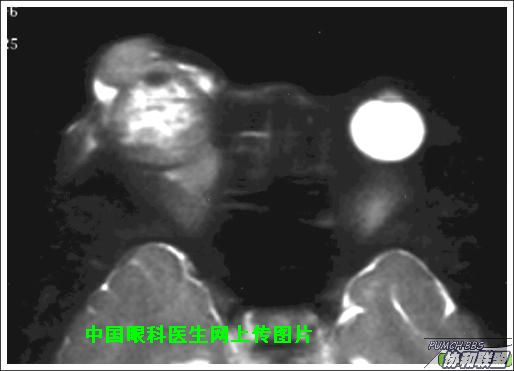

出院后半年发现右眼出现肿物,增长较快,随来京再次就诊(图1),转来我科。门诊检查发现:右眼无光感,结膜下肿物,突出睑裂。眼球突出,上移位。眶外侧可触及硬性肿物。超声(图2),CT(图3),MRI(图4,5,6)显示如图.

再询问病史,患者最初就诊前曾在当地怀疑“纵膈肿瘤”,未做手术,仅做化疗及放疗,后诊断不清。最近胸片正常。